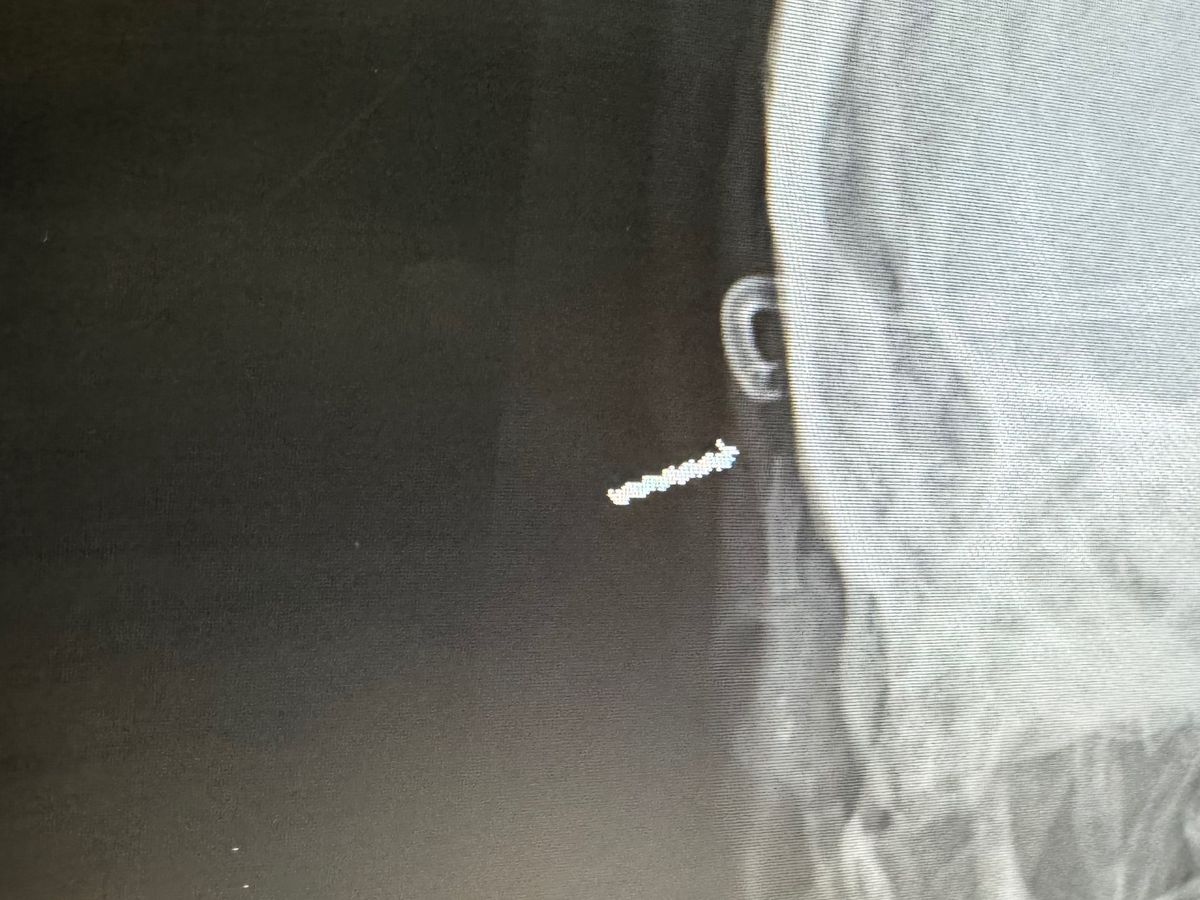

Hello my name is Michael Langley. I’m 35 years old and have lived in rock springs my whole life. I have 4 kids and a beautiful wife named Tiffany. Recently my family has fallen on pretty hard times due to medical problems with myself. Just some back history: I have had a arachnoid cyst in my brain my whole life that has required several brain surgeries. I have been good and stable for over 10 years until 2 months ago when seizures began. After meeting with neurology and neurosurgery we have found the shunt in my brain is broke which will require another brain surgery to fix. This is a long process and we have no time frame for surgery at this time. In the mean time we are having to make several trips to salt lake and they are trying to control seizures with meds.